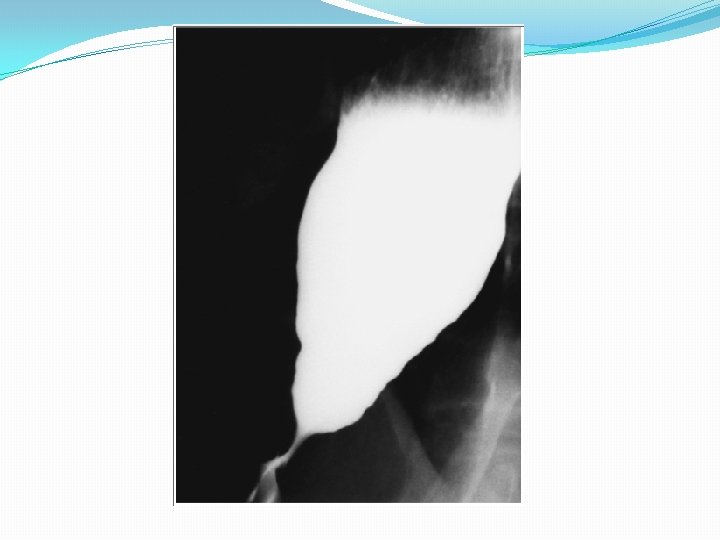

Clinical presentations dysphagia for solids and liquids and may be accompanied by undernutrition or respiratory symptoms. The mean age in children is 8. 8 yr Diagnosis 1. Chest radiograph shows an air-fluid level in a dilated esophagus. 2. Barium fluoroscopy reveals a smooth tapering of the lower esophagus leading to the closed LES, resembling a “bird's beak”.